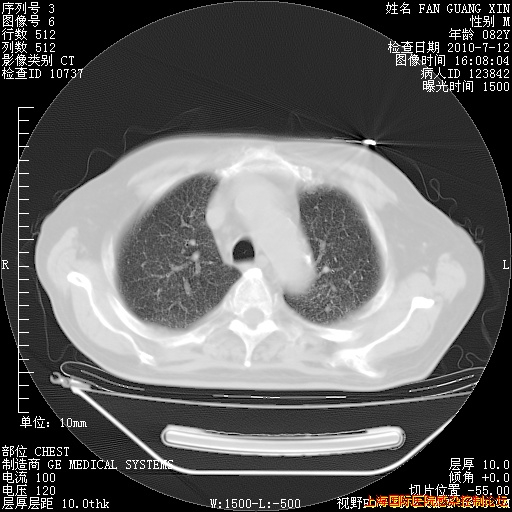

补发6月12日肺部CT肺窗

6月12日肺窗

整整相隔30天的肺部CT好像有所好转啊。甲强龙减量第3天,需要观察体温。

海管,自昨日你和我通完话后,不知您岳父消化道症状有无缓解?体温怎样?阅读7.12日胸部ct,个人认为目前激素治疗是有效的,甲强龙减量是适宜的。因在抗痨治疗,需密切观察肝功、肾功能和血常规。不过,老年、长期住院和大量使用激素,很担心菌群失调发生